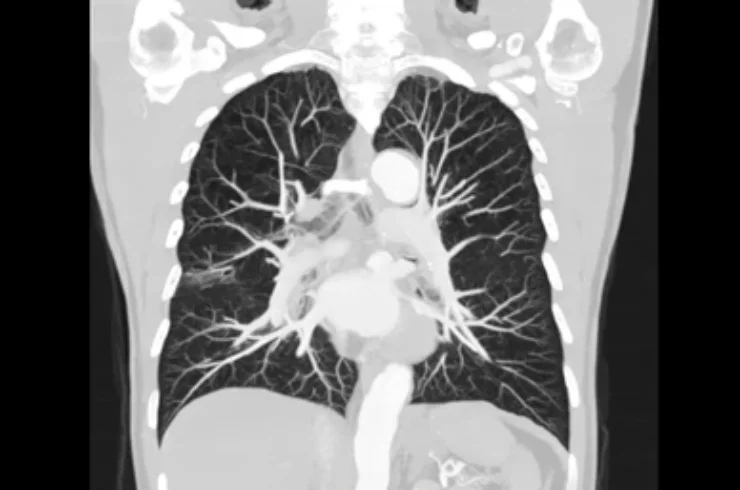

A CT Abdomen and Chest Scan is an advanced diagnostic tool that helps doctors identify a wide range of conditions affecting your internal organs. At Atharv Diagnostic Center, we use the latest CT scanning technology to obtain detailed images of your abdomen and chest, helping diagnose a variety of medical issues with precision.

A CT Abdomen and Chest Scan uses X-rays to produce cross-sectional images of your abdominal and chest regions. This scan allows your doctor to examine organs like the liver, lungs, heart, kidneys, spleen, pancreas, intestines, and more. It is particularly useful for detecting:

• Lung conditions (like tumors, infections, and inflammation)

• Heart problems (such as blockages or structural issues)

• Abdominal pain or discomfort (to identify causes like appendicitis, kidney stones, or hernias)

• Cancer detection (identifying tumors or abnormal growths)

• Infections or fluid buildup in the chest or abdomen

• Trauma or injury to internal organs

• Comprehensive View: Unlike regular X-rays, a CT scan gives doctors a 3D view of your body, allowing them to assess complex internal structures and conditions with precision.